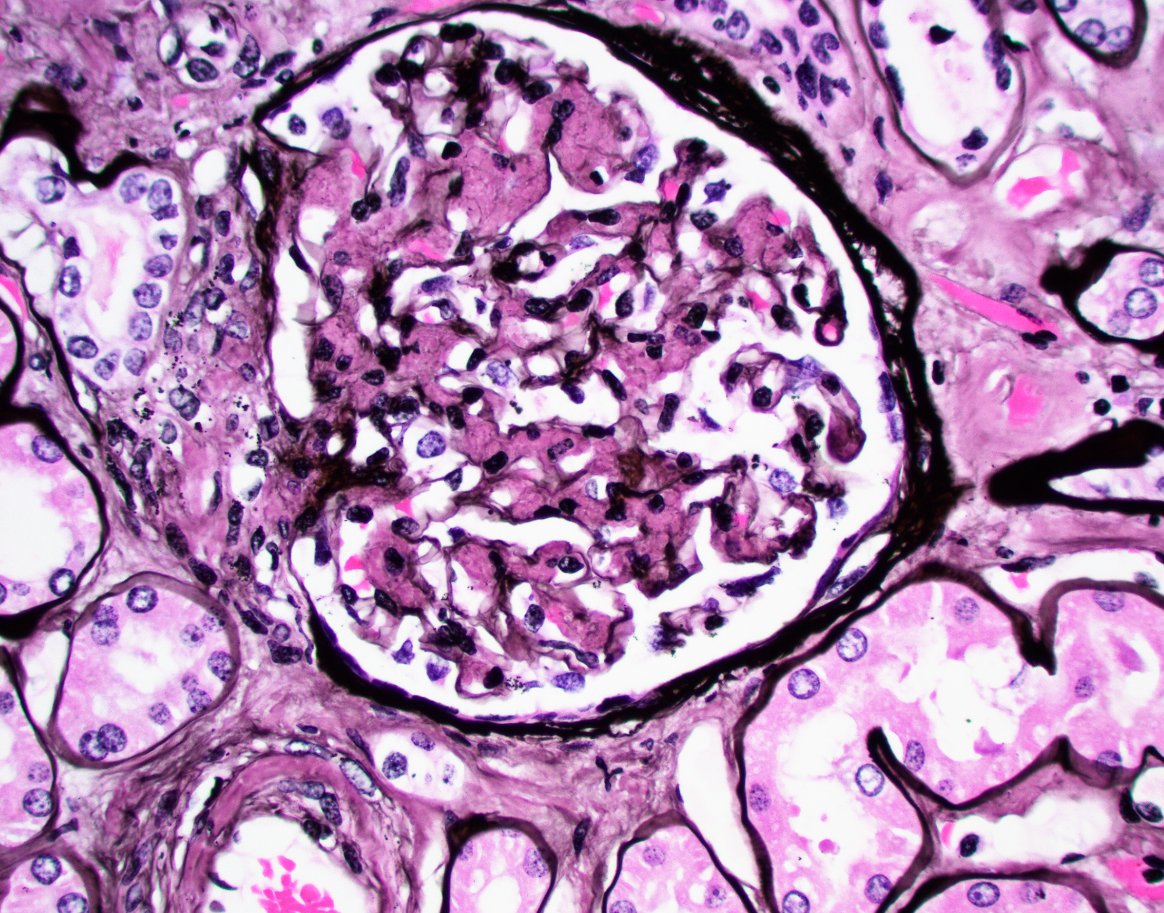

"The Banff 2024 Kidney Meeting Report: Rejection as a spectrum of phenotypes and focus on differential diagnostic reasoning," Naesens et al.